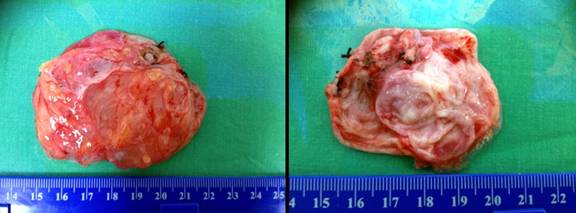

Grossly, the specimen measuring 7x6x3 cm in size was a multiloculated cystic lesion with a thin wall and contained watery clear fluid. No papillary or solid components were seen (Figure 3). Microscopically, the cyst was lined by a single layer of cuboidal cells without stratification or papillary growth (Figure 4).

Figure 3. Gross finding of the multiloculated cystic lesion with a thin wall. |